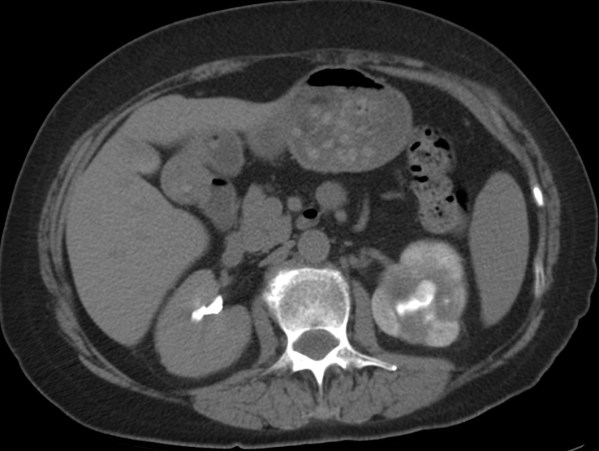

Tomografía computarizada:

Es más sensible que la ecografía y constituye la técnica de elección para detectar las calcificaciones y resto de hallazgos de la TBC renal gracias a la administración de contraste intravenoso.

Como siempre, los hallazgos varían según la afectación sea:

Precoz:

- Necosis papilar: localizada o difusa. Son cavidades necróticas localizadas en la proximidad de la papila las cuales se rellenan de constraste en fase excretora. La papila puede calcificarse posterioremente. Se observan los cálices dilatados de manera irregular.

Progresión:

- Cicatrices y estenosis que pueden afectar cualquier parte del sistema colector.

- Hidroureteronefrosis focal o generalizada.

- Áreas de poco realce en al paréquima renal (neforgama débil: áreas hipodensas cuneiformes) debido a lesión directa sobre el tejido o a la hidronefrosis.

- Retraso en la excrección de contraste.

- Engrosamiento mural del ureter (mejor valorables en TC que en la UIV)

Estadio final:

- Hidronefrosis progresiva con disminución del parénquima renal que puede simular quistes. Sirven como apoyo diagnóstico la positividad a los cultivos.

- Atrofia renal con calcificaciones que afectan a todo el riñón. Las calcificaciones extensas en un riñón no funcionante (autonefrectomía) es lo que se denomina como riñón mastic.